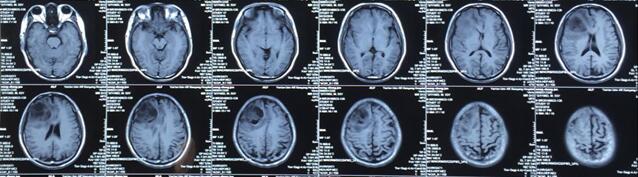

患者王某某,男,53岁,因“间断头痛半月”入神经内科十二病区,发现颅内占位后转入神经外科。既往患者有肺Ca病史,于一年前行手术治疗。头颅影像学诊断胶质瘤?转移瘤待排。2016年6月29日在3.0T磁共振定位后,刘增强副主任与其团队为患者实施了立体定向脑内病变活检术,此患者病灶为囊实性,手术难度较大,而一旦囊液流失则会发生脑组织漂移,导致靶点移位,因此手术计划制定尤为重要,入颅点为右额部,穿刺后首先达到肿瘤实性部分,获取病灶标本后,抽出部分囊液以缓解患者高颅压症状,经过精细的手术操作,最终成功获取肿瘤标本,并且抽出约20ml肿瘤液,患者情况稳定,术后两小时即下床活动。